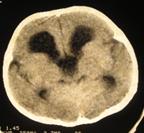

Рис.43 (а, б). аМР-томограмма головного мозга пациента с субдуральной гематомой головного мозга; бКТ пациента с эпидуральной гематомой.